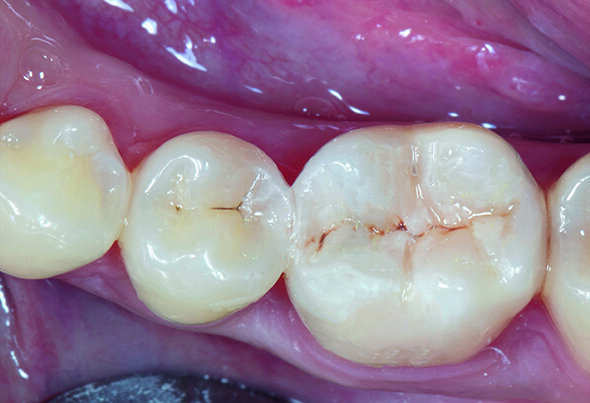

A 21-year-old female visited the dental office with a chief complaint of food lodgment and pain in tooth #46 when consuming sweet or cold food. Radiographic examination with IOPA reveled old composite restoration in tooth #46 and distal decay on #45 without involving the marginal ridge. Upon clinical examination, Class II cavities on tooth #46 & #45 were identified (Fig. 1). The most suitable treatment approach in this situation was direct restorations with bioactive composite resins.

Fig. 1. MO Class II cavity along with old composite restoration on tooth #46 and distal decay on tooth #45.